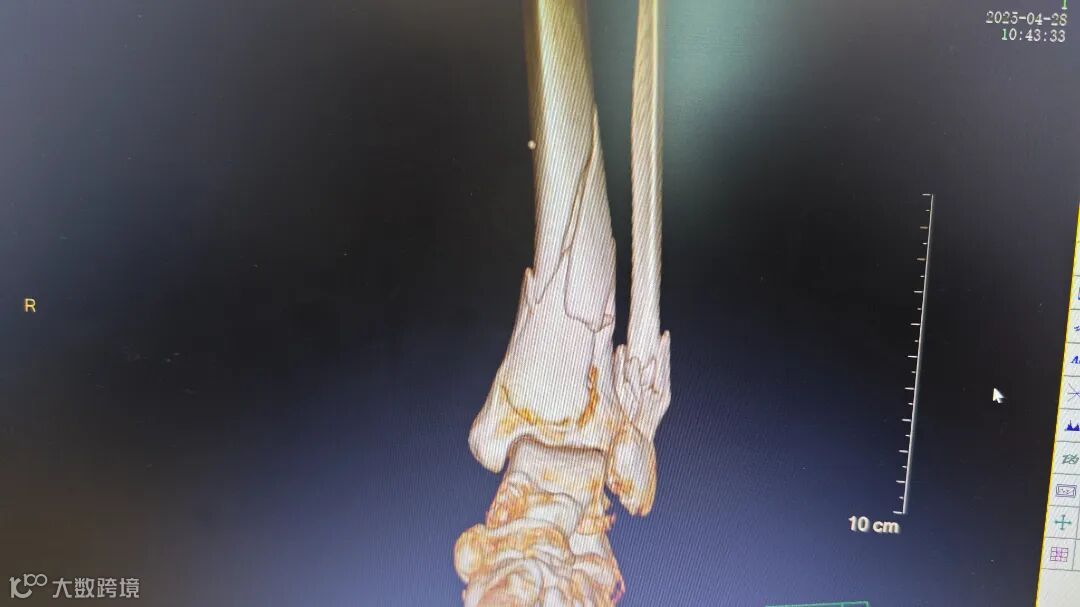

术前腿部影像

胸外科专家会诊后确认,患者肋骨骨折无明显位移,决定采用胸带固定配合卧床静养的保守治疗方案。针对更为复杂的小腿骨折,骨科团队在5月4日由张均锦主刀,曹桂青、陆仕邦医师协助下实施了精准复位手术。术中使用接骨板进行内固定后,X光显示骨折端对位良好,术后第三天患者已能进行简单的足部活动。